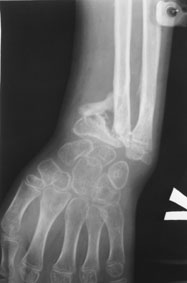

11-летний любитель лазить по деревьям 7 месяцев назад получил открытый дистальный остеоэпифизеолиз левого луча. ПХО была сделана с трудом; о репозиции, со слов, и не помышляли. Неделю назад удалось открыто адаптировать костные фрагменты, фиксировать аппаратом. Сразу сделали кортикотомию в/3 луча. Начали его удлинение. Вопрос: учитывая отсутствие дистальной зоны роста стоит ли "переудлинить" луч? Если да, то на какую величину?

как видно из Р снимков, дистальная ростковая зона повреждена. делать эпифизеодез думаю что не целесообразно. лучелоктевая косорукость преопределена, поэтому востановление придеться делать в несколько этапов. величину гиперкоррекции предусмотреть трудно не зная темпов роста, думаю что впределах 5-10мм. С уважекнием Владимир Старостенко. купянск .Харьковской. Украина

Глядя на предложенные снимки, сразу же возникает вопрос о необходимости открытого сопоставления отломков лучевой кости. Мне кажется, репозицию возможно было бы сделать и ваппарате Илизарова с использованием смещенных шарниров и этапной дистракции без выполнения разреза. Росковый хрящ, скорее всего, большей частью погиб. Но в аппарате Вы могли срепонировать и стабилизировать отломки, восстановить на время соотношение лучевой и локтевой костей в лучезапястном суставе, пусть даже дозированной осевой дистракцией.

Маленькое замечание: кортикотомия произведена (кажется так по снимку) в невыгодном с точки зрения кровоснабжения кости месте. Дитракция в аппарате приведет к сдавлению не растянутого в аппарате лучезапястного и межзапястного суставов (спица за пястные кости не проведена).